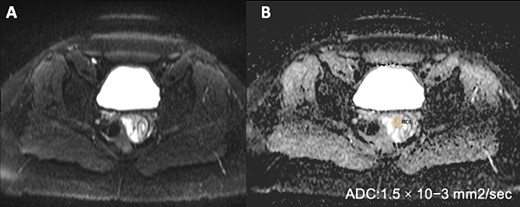

Pelvic MRI on Diffusion sequence and ADC mapping reveals no diffusion restriction, indicated by an elevated ADC value of (1.5 × 10)–3 mm2/s, suggesting benignity.

Nonetheless, when dealing with cervical polyps, conventional imaging techniques may encounter limitations due to the lesion’s challenging location. In these instances, pelvic MRI is particularly advantageous [5]. The standard MRI protocol include sagittal, oblique axial and oblique coronal views with T1 and T2 weighting, as well as diffusion and contrast sequences. Notably, Diffusion imaging is integral for distinguishing between endometrial cancer, polyps, hyperplasia and normal thickening of the endometrium [11].

Indeed, on MRI, cervical polyps are typically visualized as multicystic lesions on sagittal T2-weighted images, filling the endometrial canal or issuing from the cervix, exhibiting varied signal intensities on T1 and T2 sequences and contrast enhancement [11]. They are isointense relative to the myometrium in diffusion-weighted imaging, a feature confirmed by elevated apparent diffusion coefficient (ADC) values, aiding in their characterization [12].